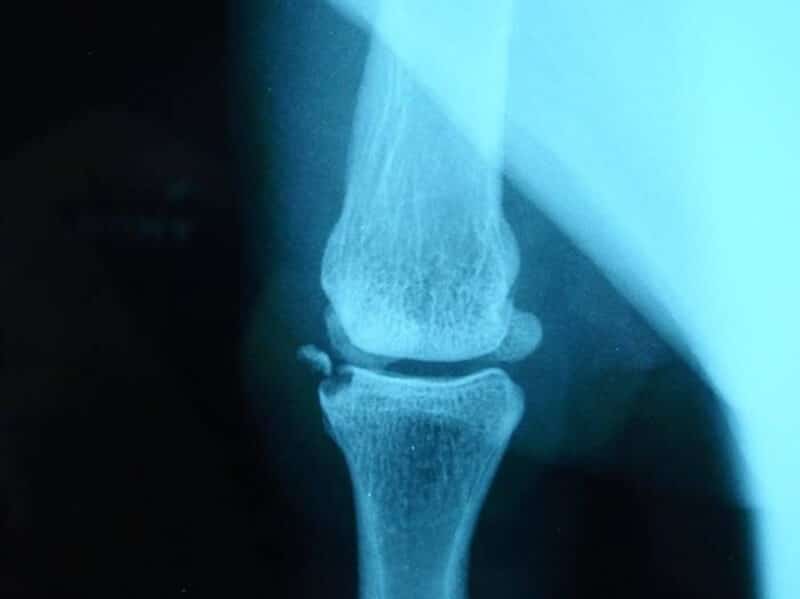

radiographie arthrose suite entorse non traitee chirurgicalement

Arthrose sévère conséquence d'une laxité chronique sur entorse mal traitée

Enfin, des douleurs chroniques peuvent apparaître, comme pour toute cicatrice. Elles sont plus fréquentes lorsque le traitement initial a été mal conduit. Une laxité persistante ou une raideur articulaire sont souvent à l’origine de ces douleurs prolongées, en raison de l’instabilité ou du manque de mobilité.